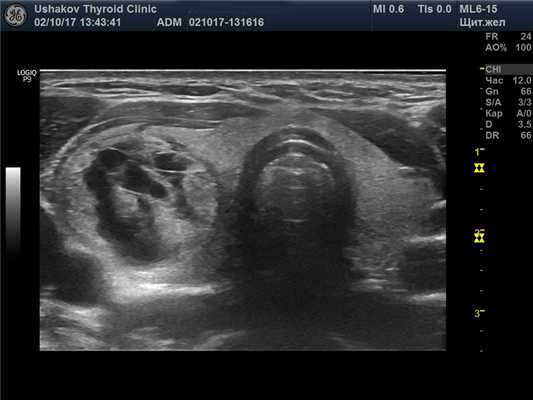

В левой доле щитовидной железы преобладает почти однородная изоэхогенная ткань, среди которой заметны два малых узла. В краниальном полюсе овоидоподобый узел 4,2х2,7х2,8 мм с чёткой границей, неоднородный: умеренно гипоэхогенный (за счёт деструкции), с малым изоэхогенным участком ткани; при ЭДК заметен крупный сосуд у края узла; при эластографии SR 2,5. Подобной организации, но более гипоэхогенный (тканевой) узел расположен в каудально-дорсальной части левой доли 2,5х2,3х4,3 мм; при эластографии SR 3,1. В режиме ЦДК и ЭДК кровообращение оптимальное.

Рис. 27.12. Пример 1. (вся щитовидная железа, поперечная проекция).

За узлом в железе – макроструктурно полноценная ткань.

4 мл макроструктурно полноценной ткани справа для этой пациентки являются абсолютной ценностью. На это указывает объём 3,2 мл левой доли. 7,2 мл всей макроструктурно полноценной ткани (без перешейка) соответствуют оптимальному объёму щитовидной железы у женщин. Поэтому важно в описании и заключении сообщать сведения о состоянии и величине этой ткани. В описании – конкретно, в заключении – общетерминологически.